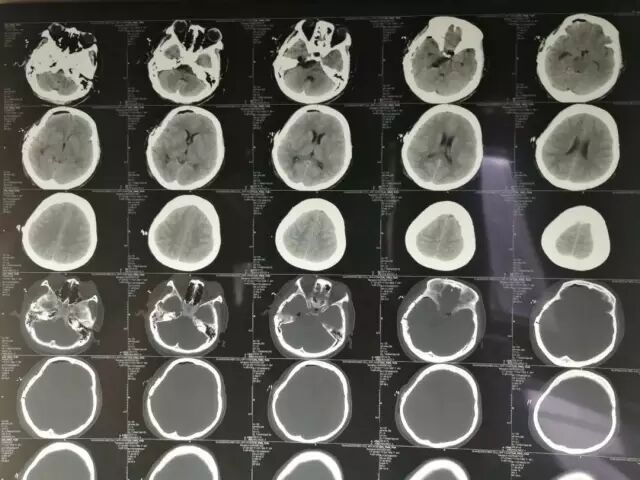

术后头颅CT扫描。